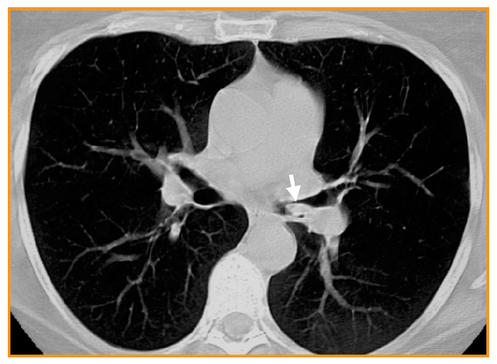

Imagerie des pathologies thoraciques chez le patient VIH ... Cette revue illustre les atteintes thoraciques infectieuses et non infectieuses chez le patient VIH au stade SIDA (moins de 200 CD4/mm 3) à l'ère des traitements antirétroviraux.Les différentes pathologies infectieuses opportunistes, tumorales et vasculaires observées chez le patient VIH ont une fréquence variable selon le degré d'immunosuppression et l'observance de la ...

Pneumopathie febrile mots fléchés. Pneumopathie organisée au sirolimus : un diagnostic à ... La pneumopathie au sirolimus, entité connue, peut se présenter sous différentes formes : apparition aiguë ou subaiguë. Elle reste un diagnostic d'exclusion. Dans notre cas, la symptomatologie principale était une altération majeure de l'état général associée à une pneumopathie unilatérale avec syndrome inflammatoire. (Pdf) Prise En Charge Radiologique Des Appendicites Aiguës ... appendicolithe (Fig. 1). Figure 1: Coupe longitudinale échographique d'un. appendice augmenté de d iamètre, à paroi épaissie, contenant du liquide et des stercolithes (flèches); en. rapport ... (PDF) Imagerie des pathologies thoraciques chez le patient ... a b Fig. 2 : Pneumopathie à Klebsiella Pneumoniae diagnostiquée en endoscopie bronchique chez un patient de 33 ans au stade sida en rupture de traitement antirétroviral (7 CD4/mm3). a Scanner thoracique montrant de multiples nodules flous, mal limités et confluents des sommets, associés à des plages de verre dépoli. (PDF) Atteintes cardiaques au cours des hyperéosinophilies ... Atteintes cardiaques au cours des hyperéosinophilies : une présentation clinique et échocardiographique polymorphe